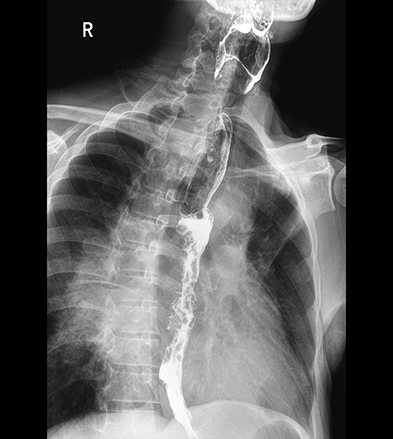

临床图像